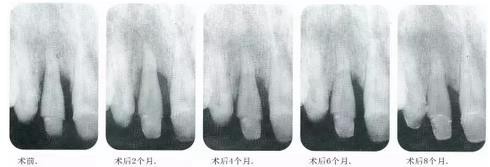

▼圖14-9~13 術(shù)后每2個月拍一次x片,檢查牙槽骨的變化??纱_認有顯著的骨增加。